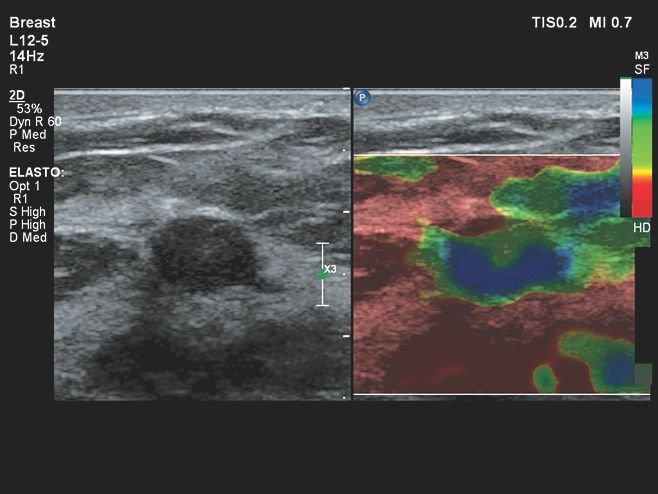

Исследования в онкологии

- Contrast GI - идеальная визуализация контрастных веществ

- Strain Elastography - эластография

- Компрессионная эластография для молочной железы и органов малого таза